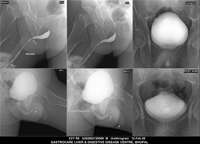

Section: URETHROGRAM Total: 95 images